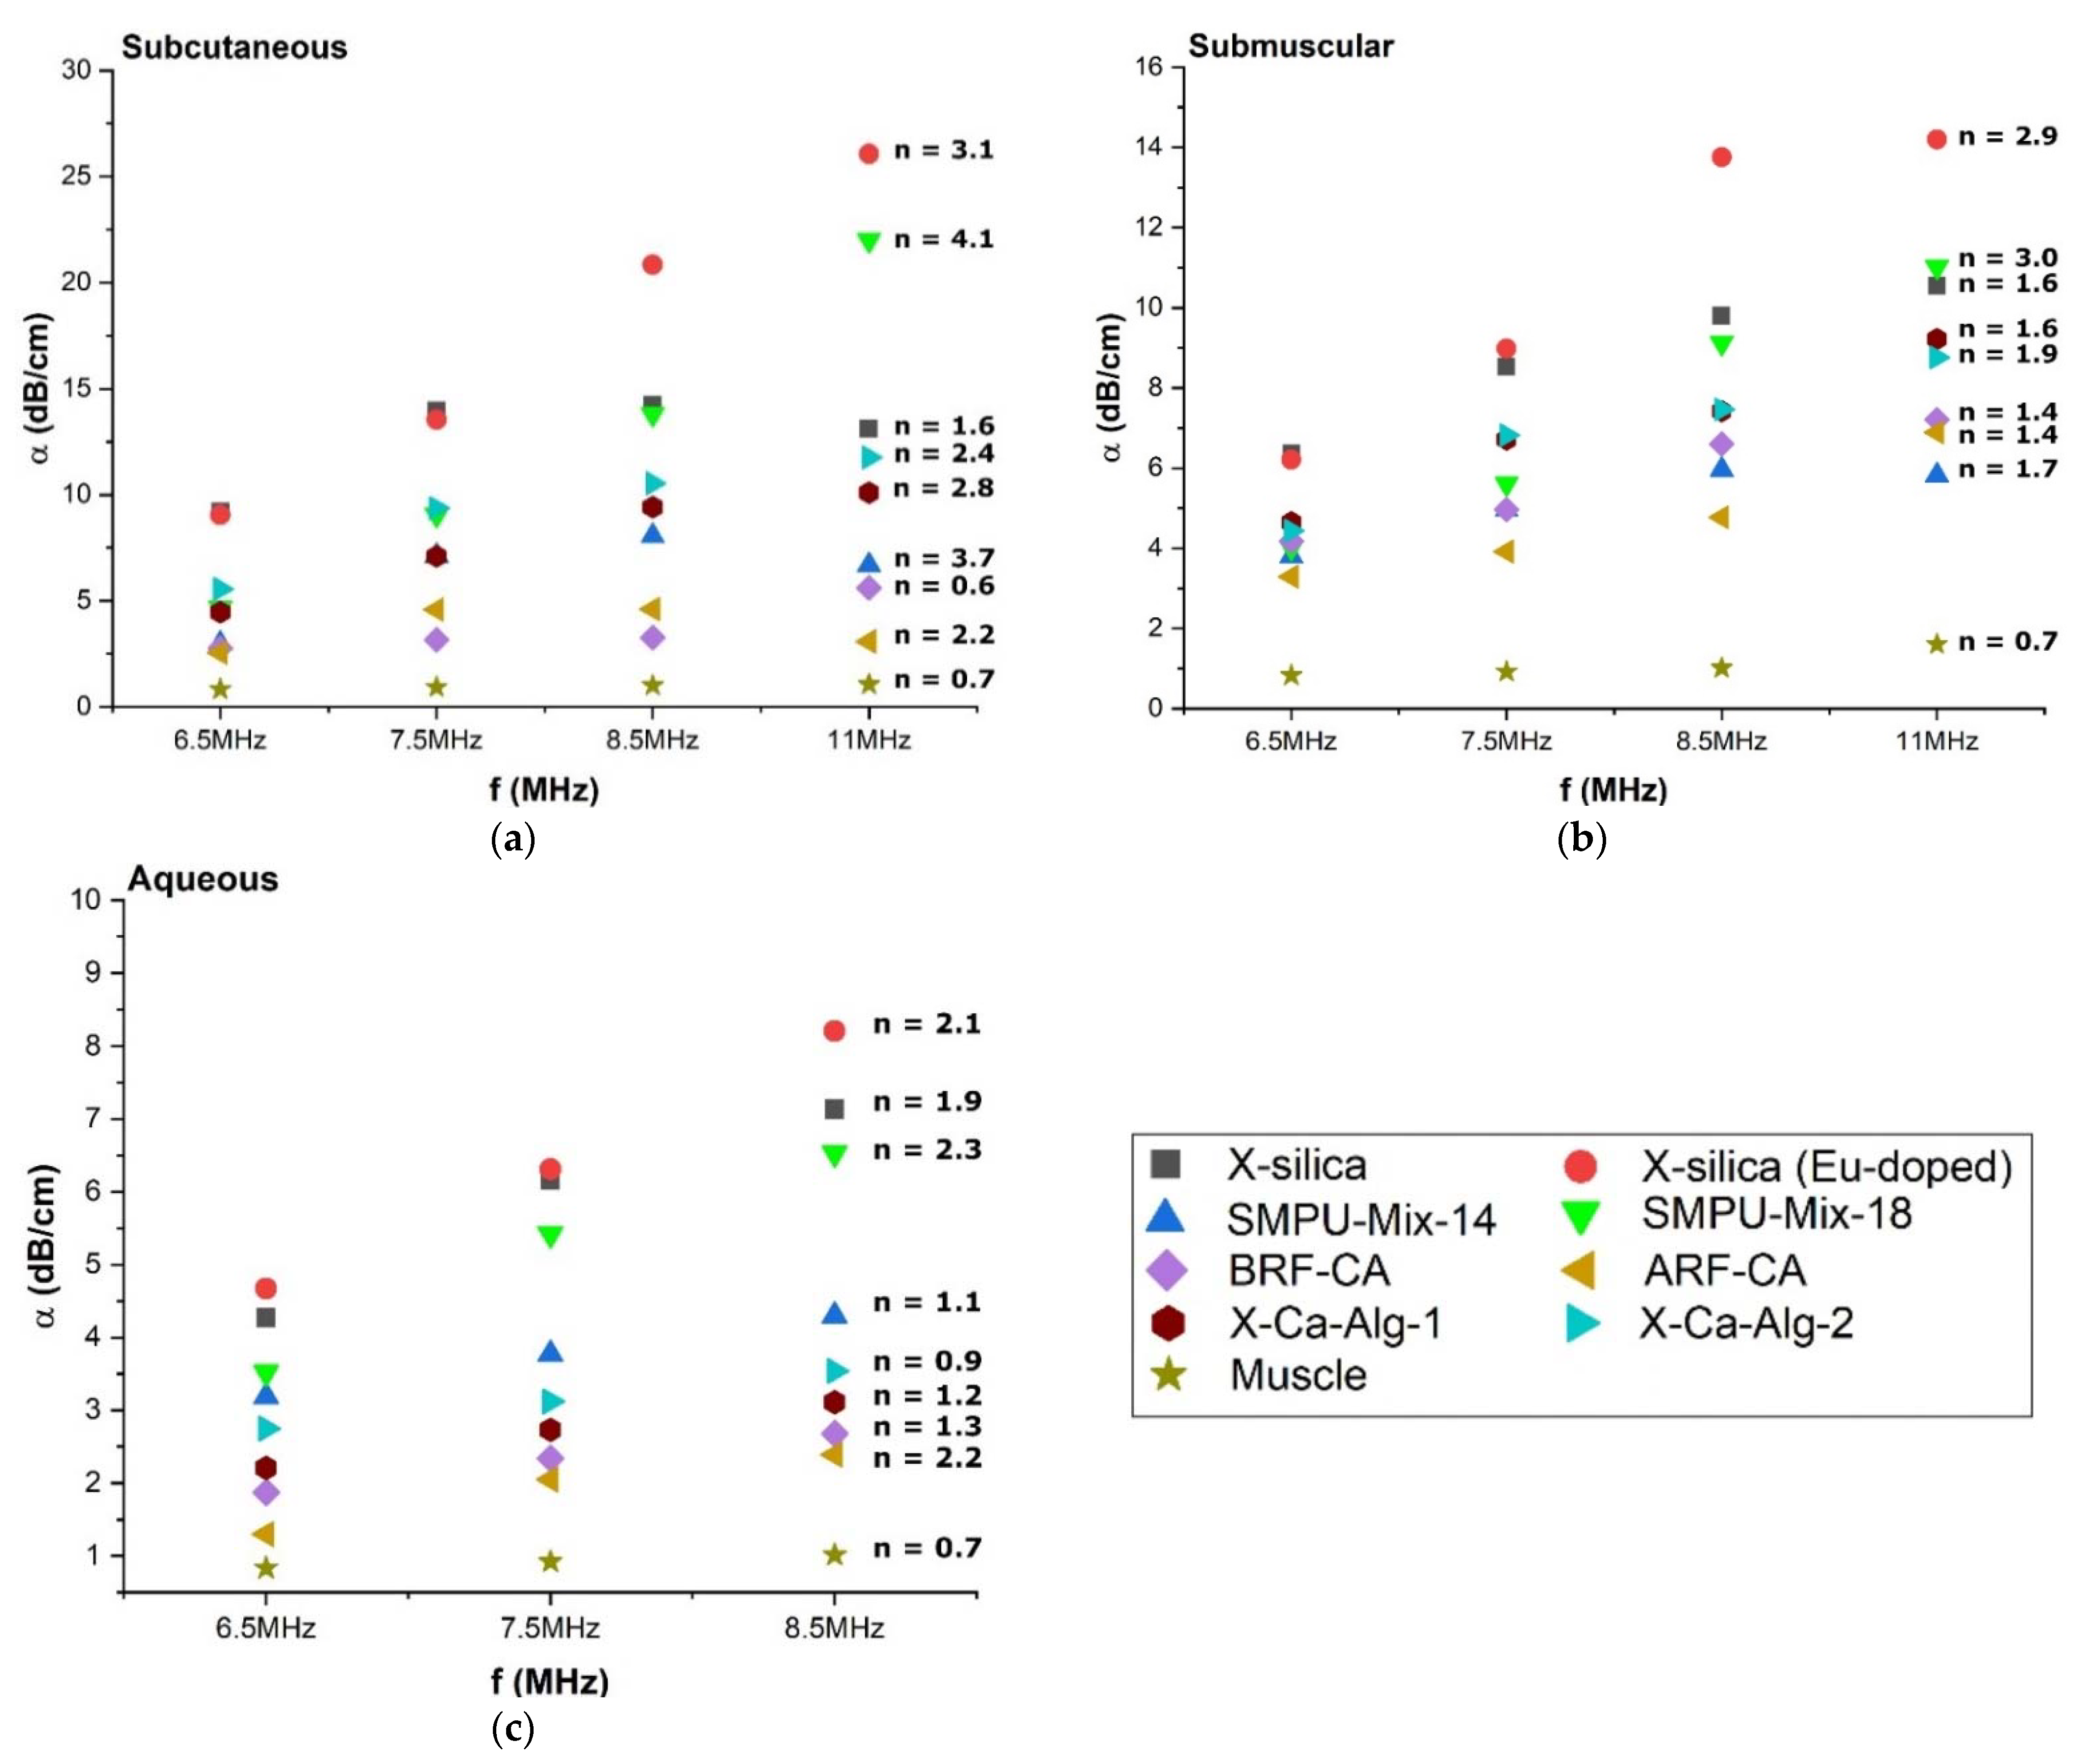

3.4. Attenuation Coefficient (α) of Aerogel Implants

3.4.1. Effect of Environments on Attenuation Coefficient (α)

3.4.2. Attenuation Coefficient (α) Dependency on Scan Frequency

4.3. Attenuation Coefficient (α) of Aerogels

4.3.1. Attenuation Coefficient (α) Comparison at Different Frequencies